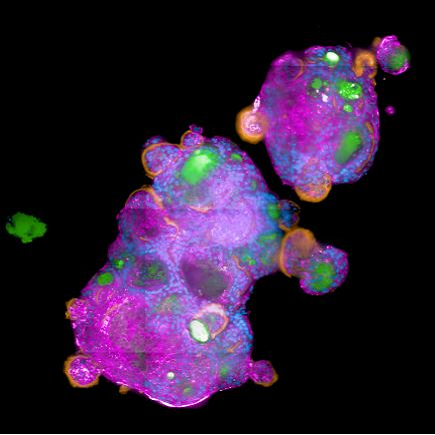

SARS-CoV-2-infected apical-out polarized lung organoids. Stained using Hoechst for nuclei (blue), MUC5AC for mucus (orange), phalloidin for tight junctions (pink), and an anti-SARS-CoV-2 antibody (green). Kindly provided by D.Wilfingseder, A.Noureen Institute of Hygiene and Medical Microbiology, Medical University of Innsbruck, Austria.